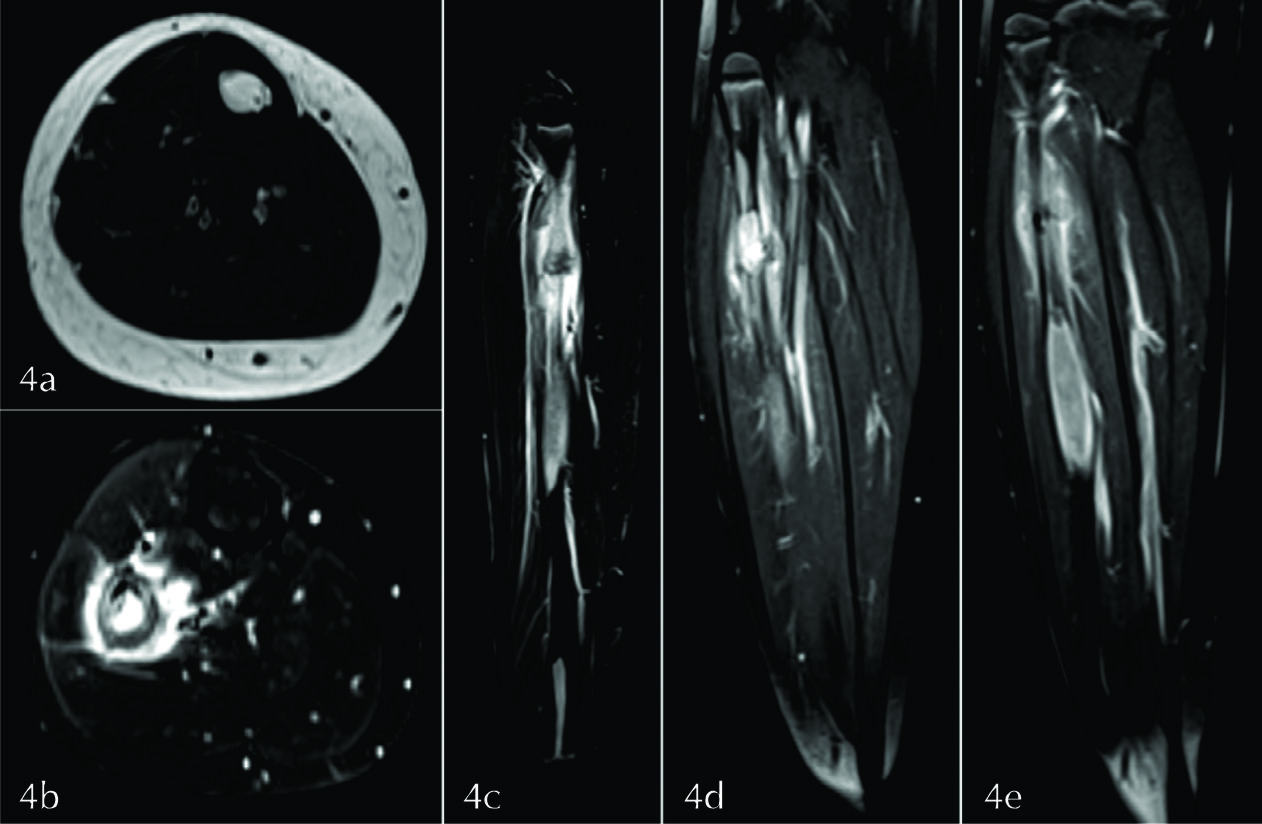

Figura 4

RM de MMII. a) Plano axial potenciado en T1 a nivel de la lesión del tercio medio del peroné, b) DP FAT SAT en el plano axial a nivel de la lesión del tercio superior, c) DP FAT SAT en el plano sagital, d y e) T1 en el plano coronal tras la administración de medio de contraste. Las lesiones son isointensas con el músculo en secuencias potenciadas en T1 (flecha amarilla), hiperintensas en DP con FAT SAT (flechas blancas), presentando realce intenso y homogéneo con el medio de contraste (flechas celestes). En la lesión superior se identifica el trazo de fractura y la reacción perióstica asociada (flecha verde), así como la presencia de edema intra óseo y de partes blandas (flechas naranjas). La lesión del tercio inferior contacta con la fisis (flecha roja).

Para evaluar con mayor precisión la extensión intra y extra ósea de la lesión, y definir su naturaleza, se decidió realizar RM. Se estudiaron ambas piernas con secuencias axiales y coronales potenciadas en T1 y DP FAT SAT, sagital DP

FAT SAT y T1 FAT SAT tras la administración de gadolinio en los tres planos del espacio (Ver fig. 4). Con el fin de determinar la distribución de las lesiones y valorar posibles lesiones en sitios insospechados se solicitó SPECT con 99Tc-MDP (Ver fig. 5). Dada la intensa captación del fémur homolateral se completó con radiografía simple de muslo derecho en proyección de frente y de perfil, identificándose lesiones radiolúcidas incipientes en la medular de la diáfisis femoral, con festoneado endóstico (Ver fig. 6).